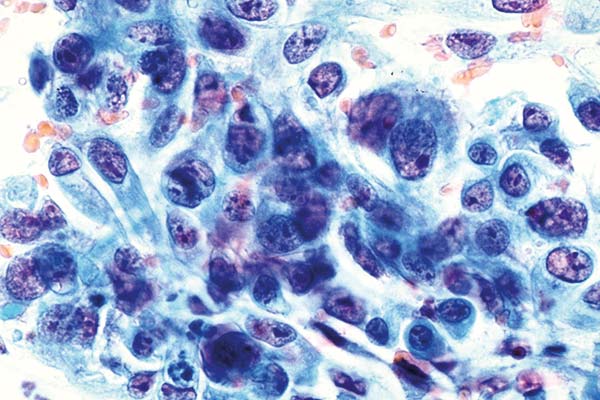

richtige Antwort:

d. nicht verhorntes Plattenepithelkarzinom, Gruppe V-p

- reichlich zyanophiles Zytoplasma

- aufgelockertes Chromatin in stark vergrößerten Zellkernen

- deutlicher Kontrast zwischen Eu- und Heterochromatin

- Tumorzellen sehr unterschiedlicher Größe und Form

- Vergrößerte Nucleoli

- Tumordiathese